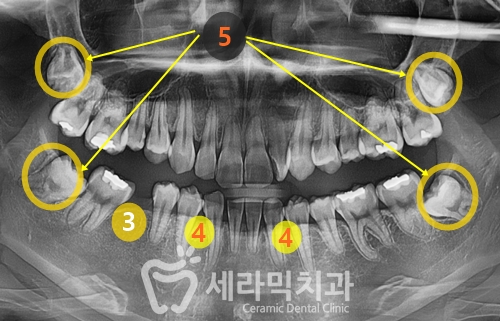

● 치료계획 상세 ●

① 치아배열 좋지 않음

② Deep bite (과개교합)

③ #46 어금니 상실 상태

④ 아래 앞니 2개가 없음

⑤ 숨은 사랑니(매복 사랑니) 있음

① 상악 교정장치 부착

② 과개교합 개선을 위한 플라스틱 교합판(ABP) 부착 +하악 교정장치 부착

③ 교정 마무리 단계에서 치아 사이 잇몸 공간(블랙트라이앵글) 발생 가능

> 치아 사이 미세 삭제 후 밀착하여 공간 문제 해결

④ #46 상실 공간을 벌린 후 임플란트 보철 필요

⑤ 예상 교정 기간 약 16~18개월